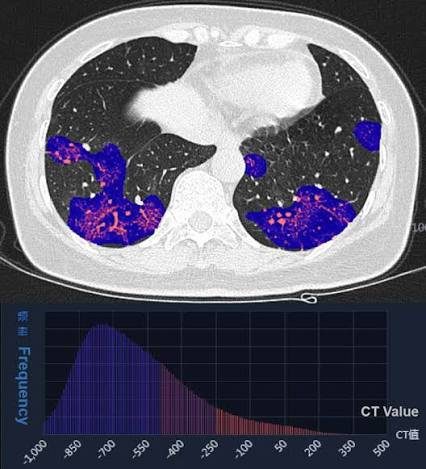

- Radiomics converts images into quantifiable data, revealing features invisible to radiologists.

Radiomics extracts features like texture, intensity, and shape from CT and PET scans. AI models use these features to predict tumor type and aggressiveness.

Pareidolia’s Role: We provide detailed segmentation and 3D modeling of tumors, enabling radiomics-based AI systems to achieve higher diagnostic accuracy.